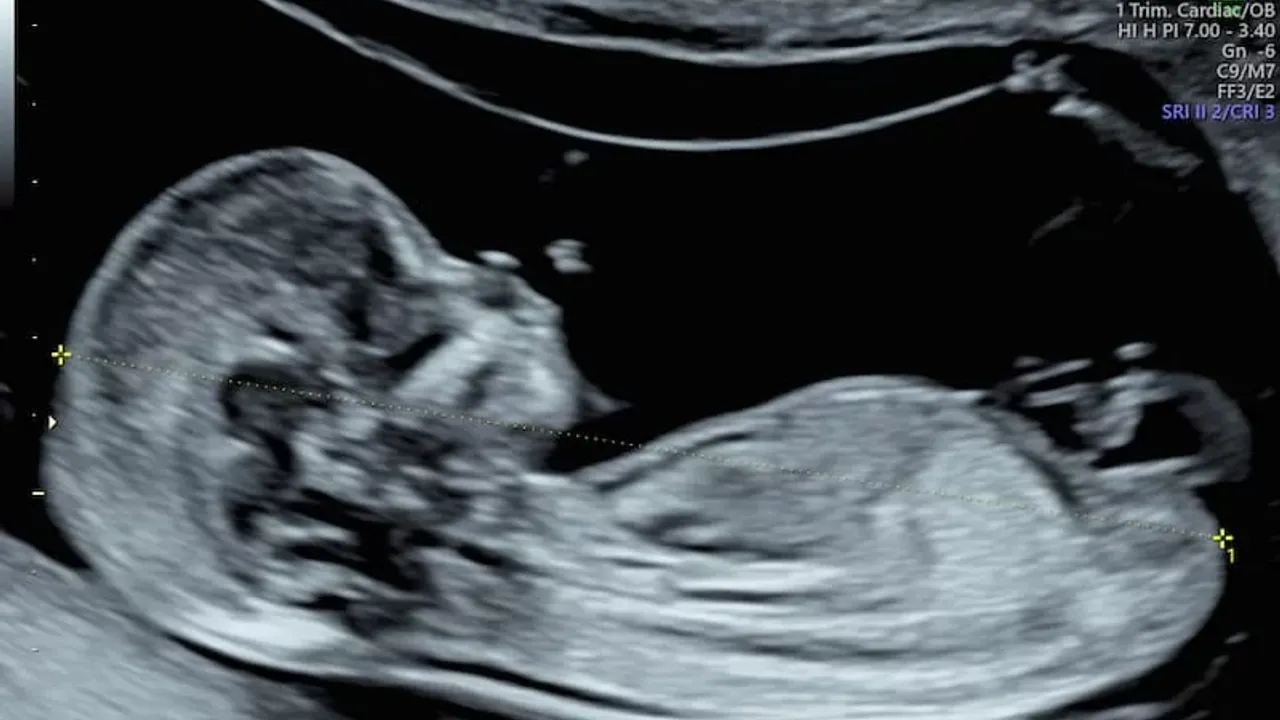

Ultrasonla Cinsiyet Ne Zaman Görülür?

Uzmanlar, bebeğin cinsiyetinin genellikle 18-22. haftalar arasında ultrason ile belirlenebileceğini söylüyor. Bu dönemde bebeğin cinsiyet organları gelişimini büyük ölçüde tamamlamış olur ve deneyimli ultrason teknisyenleri ile doktorlar cinsiyeti güvenle tespit edebilir. Ancak bazı durumlarda bebeğin pozisyonu veya anne karnındaki amniyotik sıvı miktarı, cinsiyetin net şekilde görülmesini engelleyebilir.